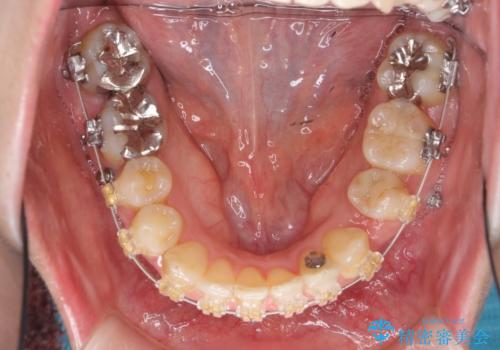

- 審美装置

- 治療期間

- 2年3ヶ月

矯正用のミニスクリューを使用し、また、前歯をIPRすることで正中の左へのずれを最小限に抑えています。